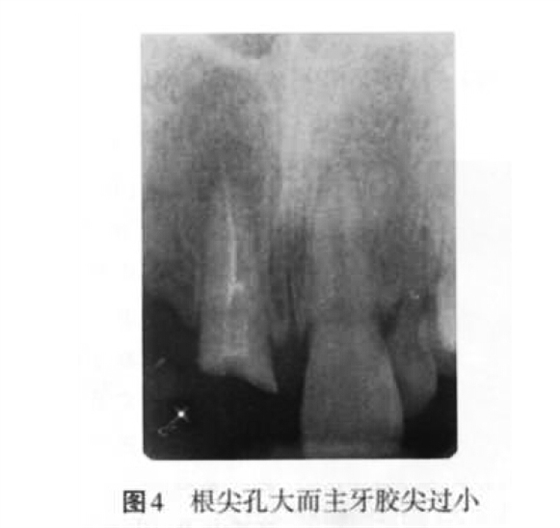

2. 2 充填止點(diǎn)不當(dāng)?shù)脑?p style="text-indent: 2em; text-align: left;">(1)欠充原因:當(dāng)根管預(yù)備不足、根管工作長(zhǎng)度測(cè)量不準(zhǔn)確(圖 3)、主牙膠尖選擇不合適、根充技術(shù)選擇不當(dāng)以及術(shù)者操作不當(dāng)時(shí),均可以導(dǎo)致欠充發(fā)生。

(2)超充原因:主要包括預(yù)備成形不良、根尖孔大而主牙膠尖過小(圖4)、根管工作長(zhǎng)度測(cè)量不準(zhǔn)確、根充技術(shù)選擇不當(dāng)以及術(shù)者操作不當(dāng)?shù)仍颉?p style="text-align:center">